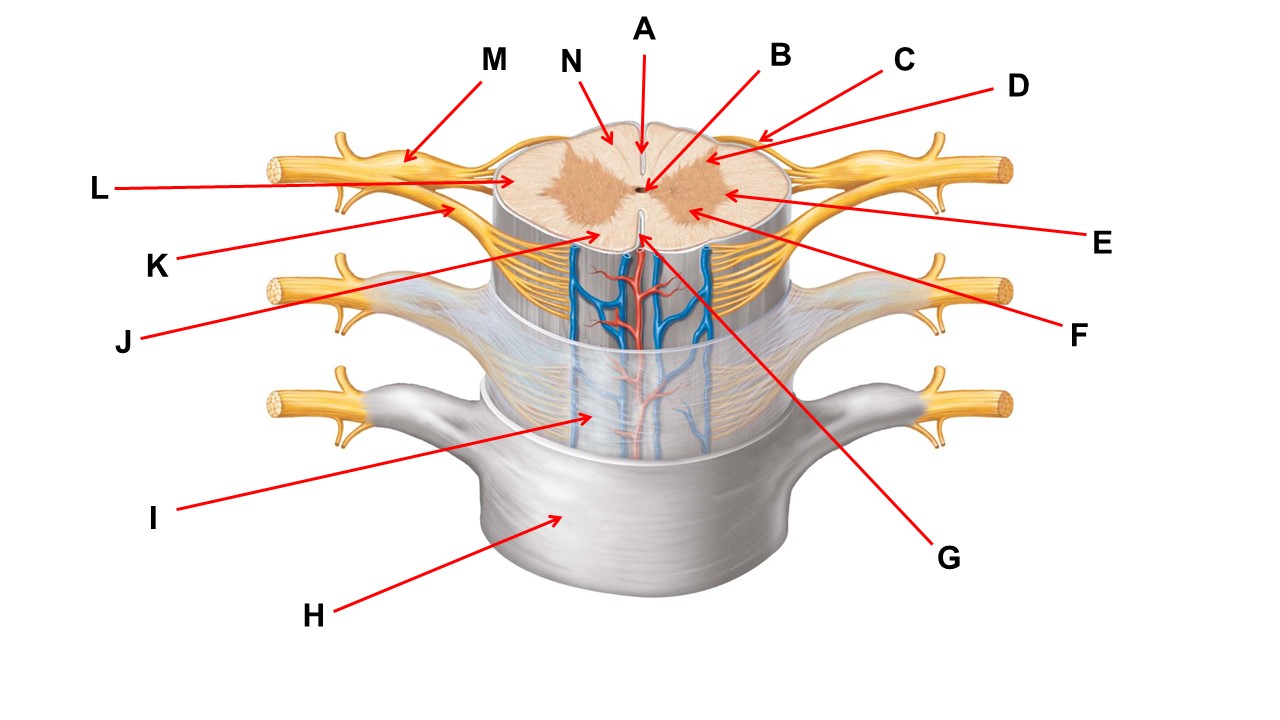

Name the region within bracket D.

Name the region of tissue surrounding the tip of arrow E.

Name the region of tissue surrounding the tip of arrow B.

dorsal horn

Name the structure at the tip of arrow K.

ventral root

Name the region of tissue surrounding the tip of arrow J.

ventral column

Name the region of tissue surrounding the tip of arrow E.

lateral horn

Name the region of tissue surrounding the tip of arrow N.

dorsal column

Name the deep groove at the tip of arrow G.

anterior median fissure

Which structure(s ) would be found in the area at the tip of arrow D.

cell bodies of interneurons

Name the region of tissue surrounding the tip of arrow E.

ventral horn

Name the region within bracket G.

gray commisure